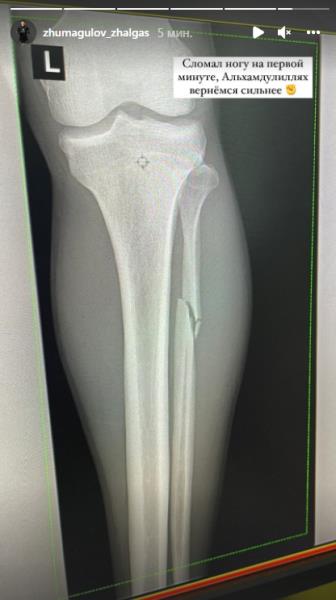

«Сломал ногу на первой минуте. Альхамдулиллах, вернёмся сильнее», — написал «Жако» на своей странице в Instagram, где также опубликовал рентген-снимок своей повреждённой ноги.

Казахстанский боец UFC Жалгас Жумагулов (14-6) сообщил о полученной травме в поединке с ангольским файтером Манелом Капе (17-6), передает Sports.kz.

Напомним, бой Жумагулов — Капе состоялся в минувшие выходные на турнире UFC on ESPN 31 в Лас-Вегасе (США) и завершился поражением казахстанца нокаутом в первом раунде. Для Жумагулова это поражение стало первым досрочным в UFC.